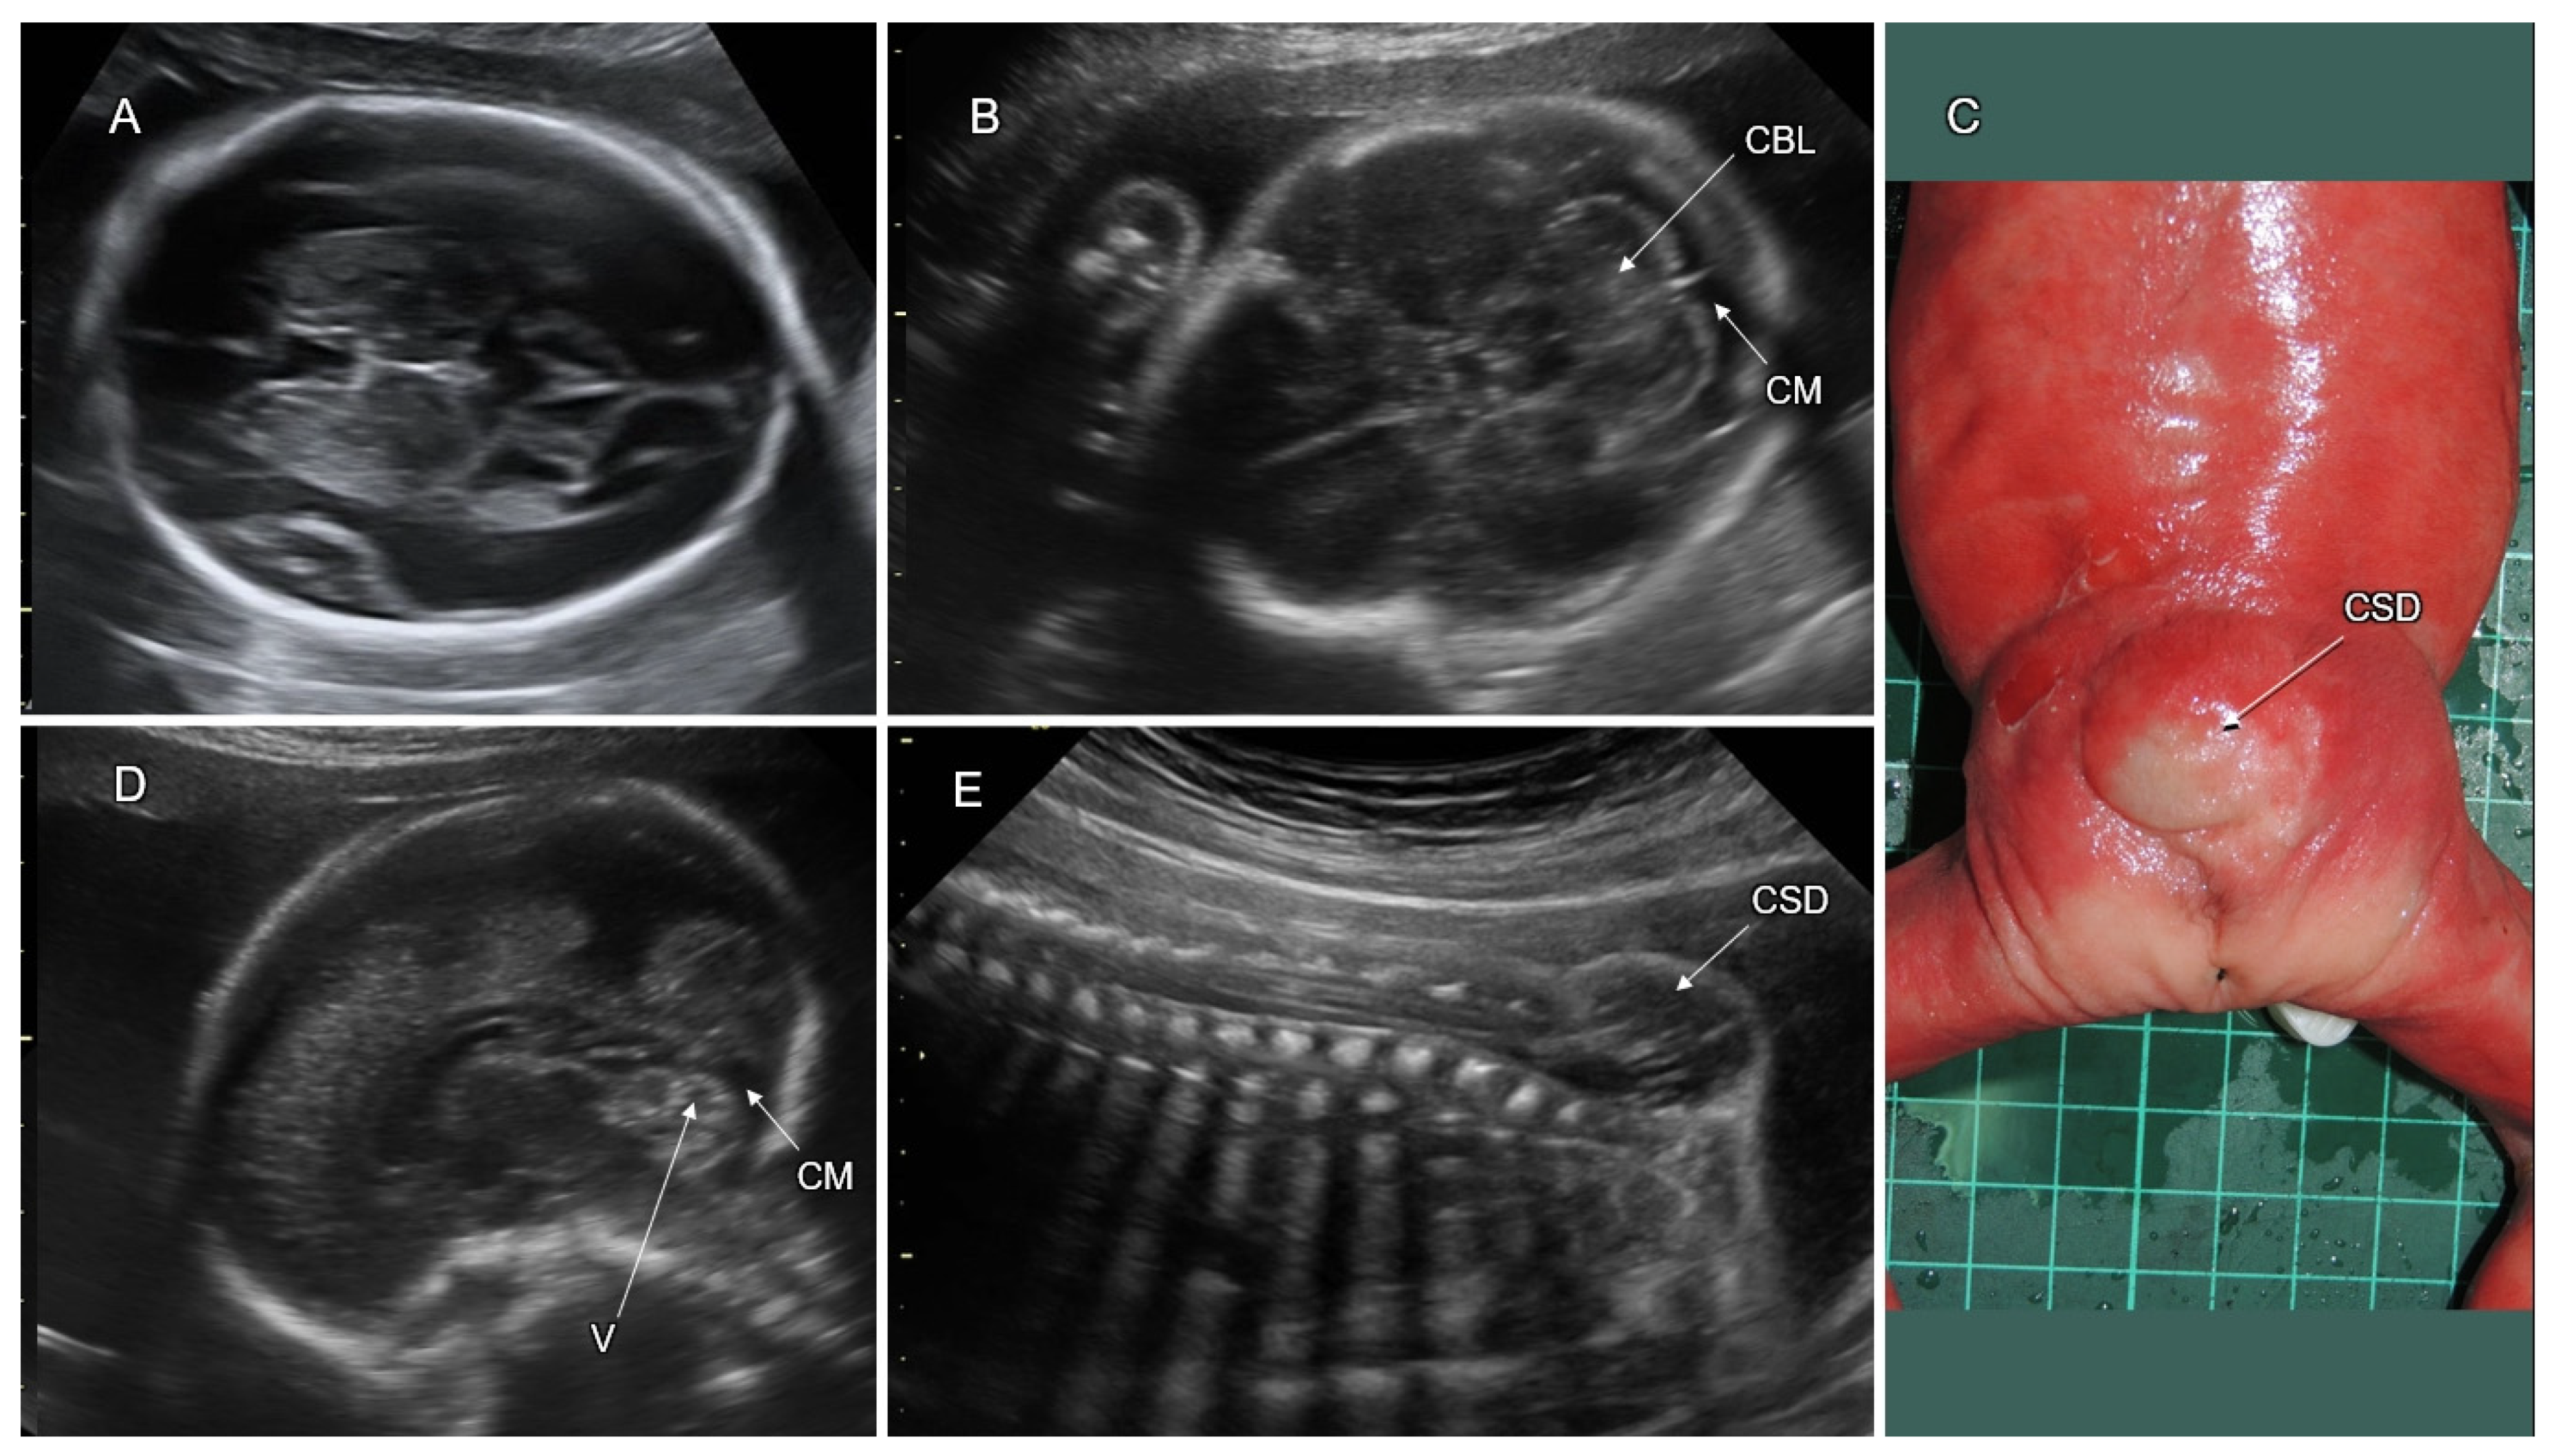

6.2.2. Cobblestone Malformation (CM)